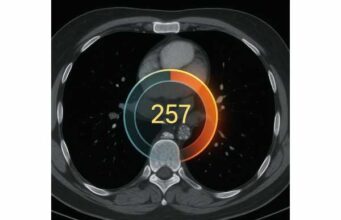

Genetics can guide prevention, but not all tests deserve space in your budget. Start with actionable genetics—variants with clear management implications. For cardiovascular and brain aging, two standouts are APOE and pharmacogenomics panels relevant to lipid, antihypertensive, and antiplatelet therapy. APOE ε4 raises lifetime risk for Alzheimer’s disease and accelerates atherosclerosis in some people; the utility is not in predicting destiny but in motivating earlier, aggressive risk control (ApoB, blood pressure, sleep, activity) and in caution with head injury, alcohol, and poorly controlled sleep apnea. Pharmacogenomics can flag clopidogrel nonresponse (CYP2C19 loss-of-function) or statin myopathy risk (SLCO1B1 variants) and inform drug choice. Coronary artery calcium (CAC) is not genetics but functions like a biological age stamp for your arteries. A CAC of zero in midlife suggests low 10-year event risk; detectable calcium reclassifies you upward and strengthens the case for LDL/ApoB lowering and lifestyle intensity. CAC does not replace lipids; it puts your current burden of disease on the table. If you do CAC, focus on the management decision it informs—therapy intensity, not chasing the number every year. For when to scan and how to act on scores, see coronary artery calcium for longevity. Beyond these, use selective advanced testing when a clinical question is on the line:- Lipoprotein(a) genotyping is redundant if you have a reliable Lp(a) level; phenotype drives decisions.